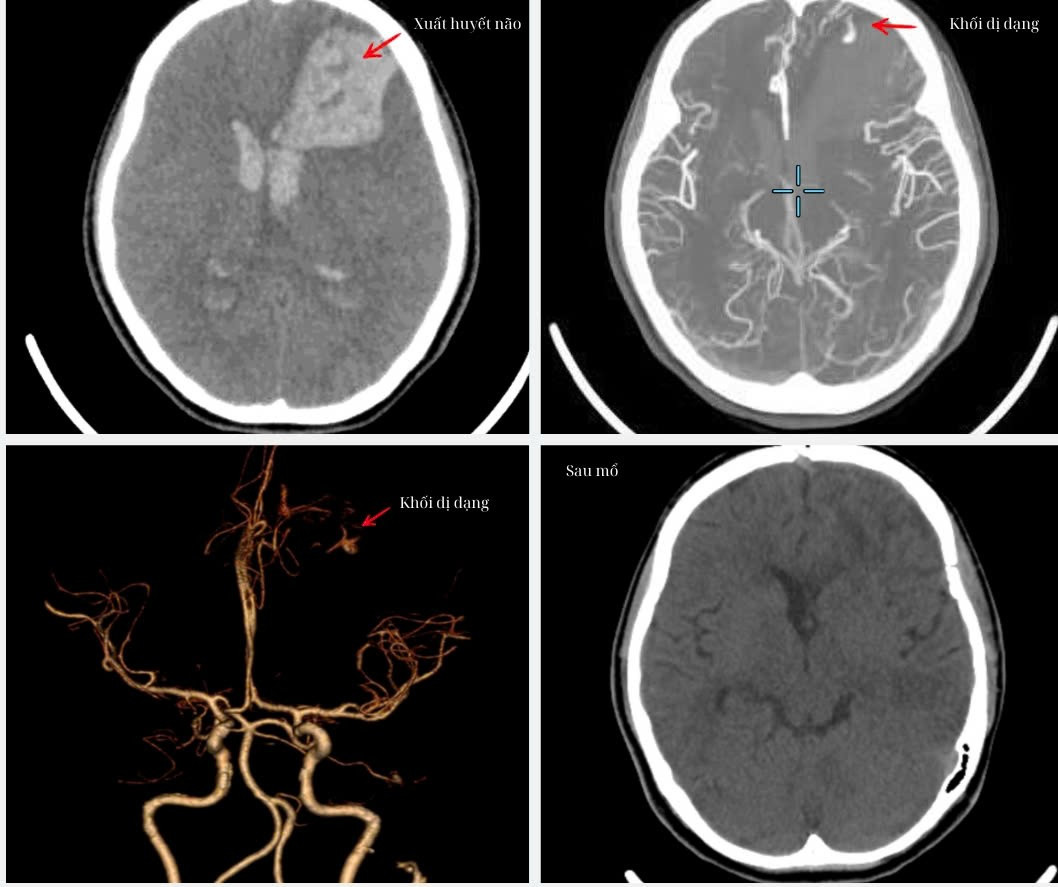

Khối dị dạng mạch máu não của bệnh nhân được bác sĩ phát hiện trên hình ảnh kiểm tra

Qua hình ảnh chụp MSCT mạch máu não các bác sĩ phát hiện em V. bị xuất huyết não cấp vùng trán trái do vỡ dị dạng động – tĩnh mạch não, máu đã tràn vào não thất, đường giữa lệch 10mm, não thất giãn cấp tính.